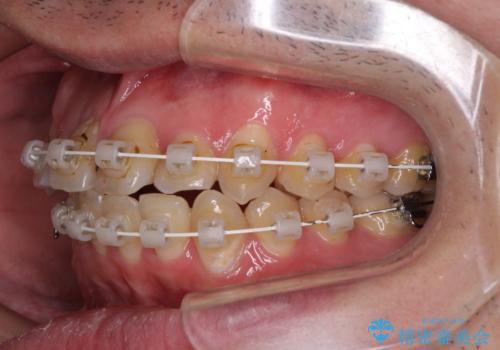

クロスバイトは、治療の過程で咬み合わせが大きく変化する期間があり、食事が取りにくくなってしまいます。

また、装置が対合歯と咬み合ってしまい、頻繁に脱落するなど、色々と面倒なことがあり、治療がスムーズに進まないことがあります。